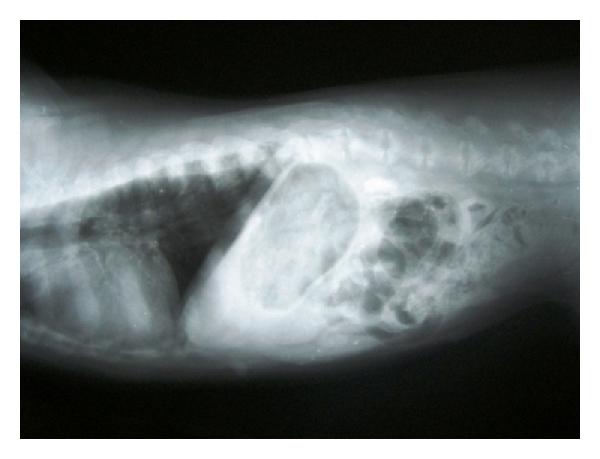

Hepatic disease is often treatable and has a predictable prognosis when a definitive diagnosis is made. The aim of clinicopathological evaluation of hepatobiliary affections is to identify and characterize hepatic damage and dysfunction, identify possible primary causes of secondary liver disease, differentiate causes of icterus, evaluate potential anaesthetic risks, assess prognosis and response to xenobiotics, and monitor response to therapy. This paper describes the different diagnostic methods and imaging techniques employed in diagnosis of hepatobiliary affections in dogs. Besides reviewing the significant clinical manifestations and imaging structural abnormalities in diagnostic approach to different hepatic affections, it also depicts radiographic, ultrasonographic, and wherever applicable, the laparoscopic characterization of different hepatic affections and target lesions encountered in clinical cases presented in the Teaching Veterinary Clinical Complex, COVAS, Palampur in the year 2007-2008.

肝病通常是可治疗的,一旦做出明确诊断,其预后是可预测的。肝胆疾病临床病理评估的目的是识别和描述肝损伤及功能障碍,确定继发性肝病可能的主要病因,鉴别黄疸的病因,评估潜在的麻醉风险,评估预后及对外源化学物质的反应,并监测治疗反应。本文描述了用于诊断犬肝胆疾病的不同诊断方法和成像技术。除了回顾不同肝病诊断方法中的重要临床表现和成像结构异常外,还描述了2007 - 2008年在帕兰普尔兽医临床综合教学中心(COVAS)出现的临床病例中不同肝病及目标病变的放射学、超声学特征,以及在适用情况下的腹腔镜特征。